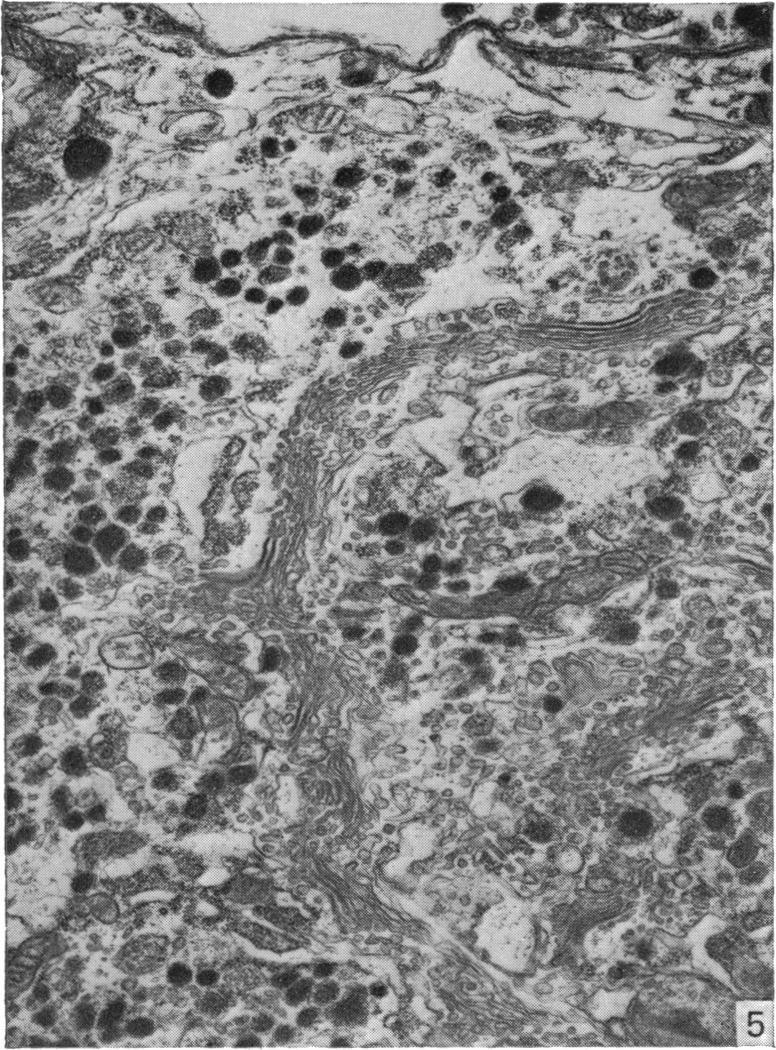

A technique is described which permits the maintenance for up to 8 days in organ culture of explanted rat pituitary glands. Electron microscope studies showed that the cultured glands (whether treated with gonadotrophin-releasing hormone (GnRH) or not) were almost identical to controls in appearance, although the stellate (follicular) cells seemingly were eliminated in vitro. Gonadotrophs and prolactin-secreting cells in male and female pituitary glands were similar in appearance both in vivo and in vitro to comparable cells described by other authors. There was some evidence for an increase in the secretory activity of these cell types (particularly gonadotrophs) when the explants were treated with GnRH. The present technique thus provides a suitable and valid 'model' with which to study the effects of GnRH and steroid hormones on the release and synthesis of FSH and LH in vitro.

本文描述了一种技术,该技术可使离体大鼠垂体腺在器官培养中维持长达8天。电子显微镜研究表明,培养的腺体(无论是否用促性腺激素释放激素(GnRH)处理)外观上与对照几乎相同,尽管星状(滤泡)细胞似乎在体外被清除。雄性和雌性垂体腺中的促性腺激素细胞和催乳素分泌细胞在体内和体外的外观与其他作者描述的同类细胞相似。有证据表明,当外植体用GnRH处理时,这些细胞类型(特别是促性腺激素细胞)的分泌活性会增加。因此,本技术提供了一个合适且有效的“模型”,用于研究GnRH和类固醇激素对体外FSH和LH释放与合成的影响。